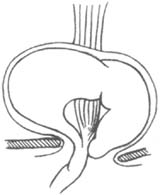

较大的滑动型裂孔疝在病人休息状态下,即可在钡餐检查时发现,有一个>3cm的胃囊突入胸腔,常伴有没程度的胃食管返流每时征。手术中可发现这些病例的膈食管膜,其伸入食管壁的位置较正常人靠近胃食管接合部,这样低位的伸入,是否为先天性或后天性因素造成尚不清楚。此疝较少见,约占全部裂孔疝的2%,但由于腹内脏器疝入胸腔,故有重要的临床意义。此疝的膈食管有缺损,通常在裂孔的左前方,偶尔在右后面。由于此缺损的存在,使腹膜能通过此缺损成为真正的疝囊,相邻的胃也通过此筋膜的缺损疝入胸腔(图4)。由于膈食管膜不能长期限制上移的胃,而且在部分时间胸腔压力低于腹腔压力,此缺损必然进行性扩大。在后期,全胃均可疝入胸腔,而贲门仍被膈食管膜部分固定在原处,幽门已向其靠近,胃可以发生旋转、扭转、梗阻和缩窄,胸胃扩张破裂,如延误诊治,任何一种并发症均可导致死亡(图5)。正由于上述原因,即使尚无明显症状的食管旁疝,也应考虑及早手术。

图4 食管旁疝